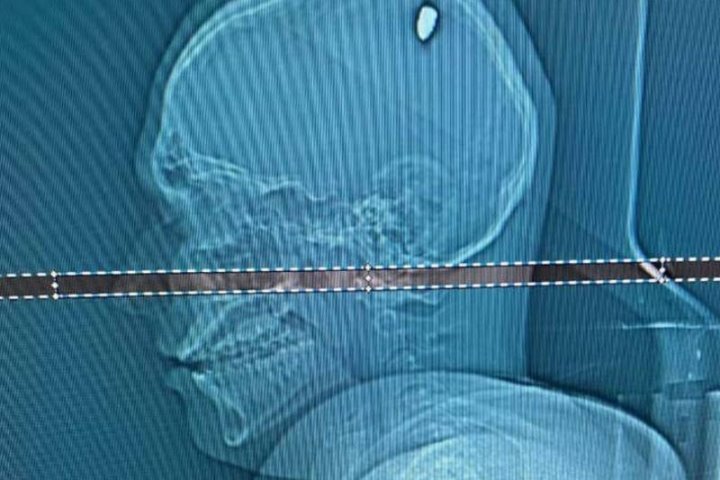

На томографии выяснилось, что источником проблемы была пуля, застрявшая в одной из некритичных частей мозга. Ее извлекли хирургическим путем. Операция прошла успешно, и Матеус уже находится на пути к полному выздоровлению.